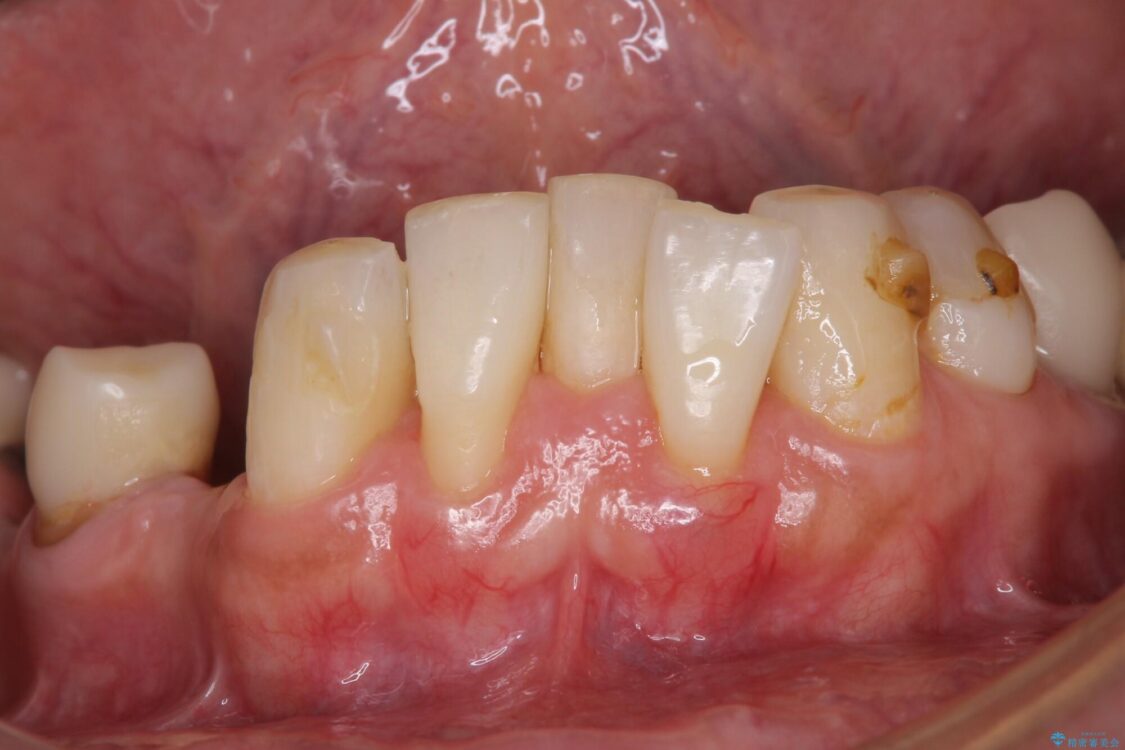

治療前

• 放置したインプラントとインビザライン 全顎リカバリー治療 治療前画像